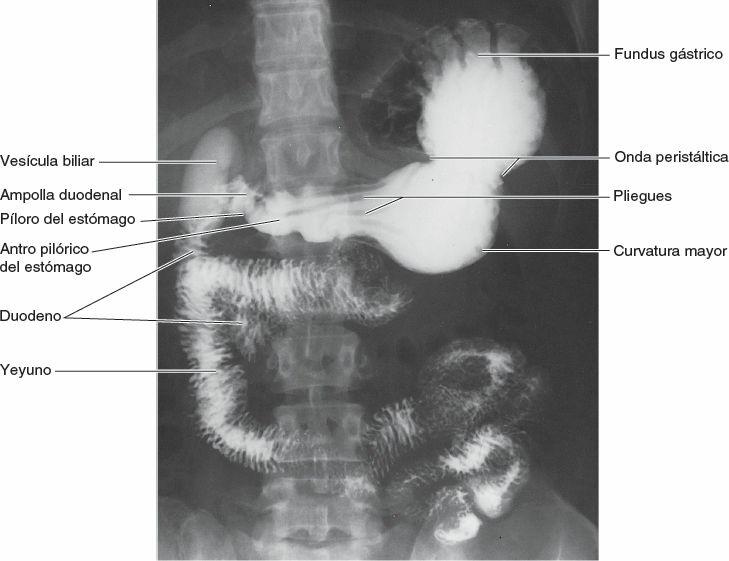

La introducción de medios de contraste (líquidos radiopacos, como compuestos de yodo o bario) permite estudiar diversos órganos luminales o vasculares y espacios potenciales o reales (como el tubo digestivo, los vasos sanguíneos, los riñones, las cavidades sinoviales y el espacio subaracnoideo) que no son visibles en las radiografías simples (fig. 1-52). En la mayoría de las exploraciones radiológicas se emplean al menos dos proyecciones, en ángulo recto entre ellas. Como cada radiografía es una representación bidimensional de una estructura tridimensional, las estructuras que atraviesa secuencialmente el haz de rayos X se superponen. Por lo tanto, suele ser necesaria más de una proyección para detectar y localizar con precisión las anomalías.